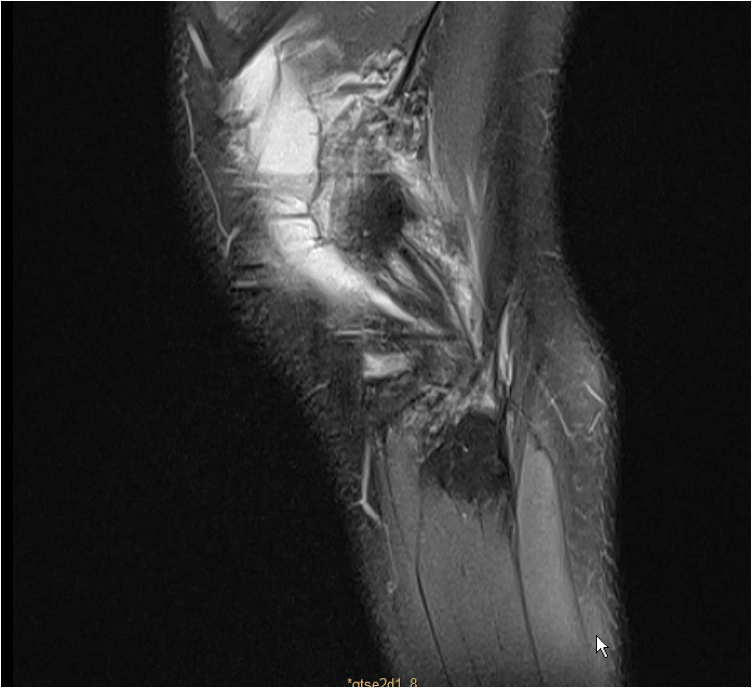

• 24 Y.O male

• Professional freestyle skier

• ACL reconstruction with harmstrings 18 months ago

• Knee torsional trauma skiing

• On physical examination, he presents a positive Lachman test and a grade 3 pivot shift test

In this case, our choice was to perform a one-time ACL revision with a hybrid graft composed by the iliotibial band left attached and a gracilis allograft. An outside-in femoral tunnel has been performed, and the same tibial tunnel has been used as it was well positioned. This technique is easy to perform and allows to do a lateral tenodesis and an ACL reconstruction with the same graft, and to avoid a femoral tunnel convergence. A meniscal ramp lesion and a lateral meniscal tear have been sutured at the same time.